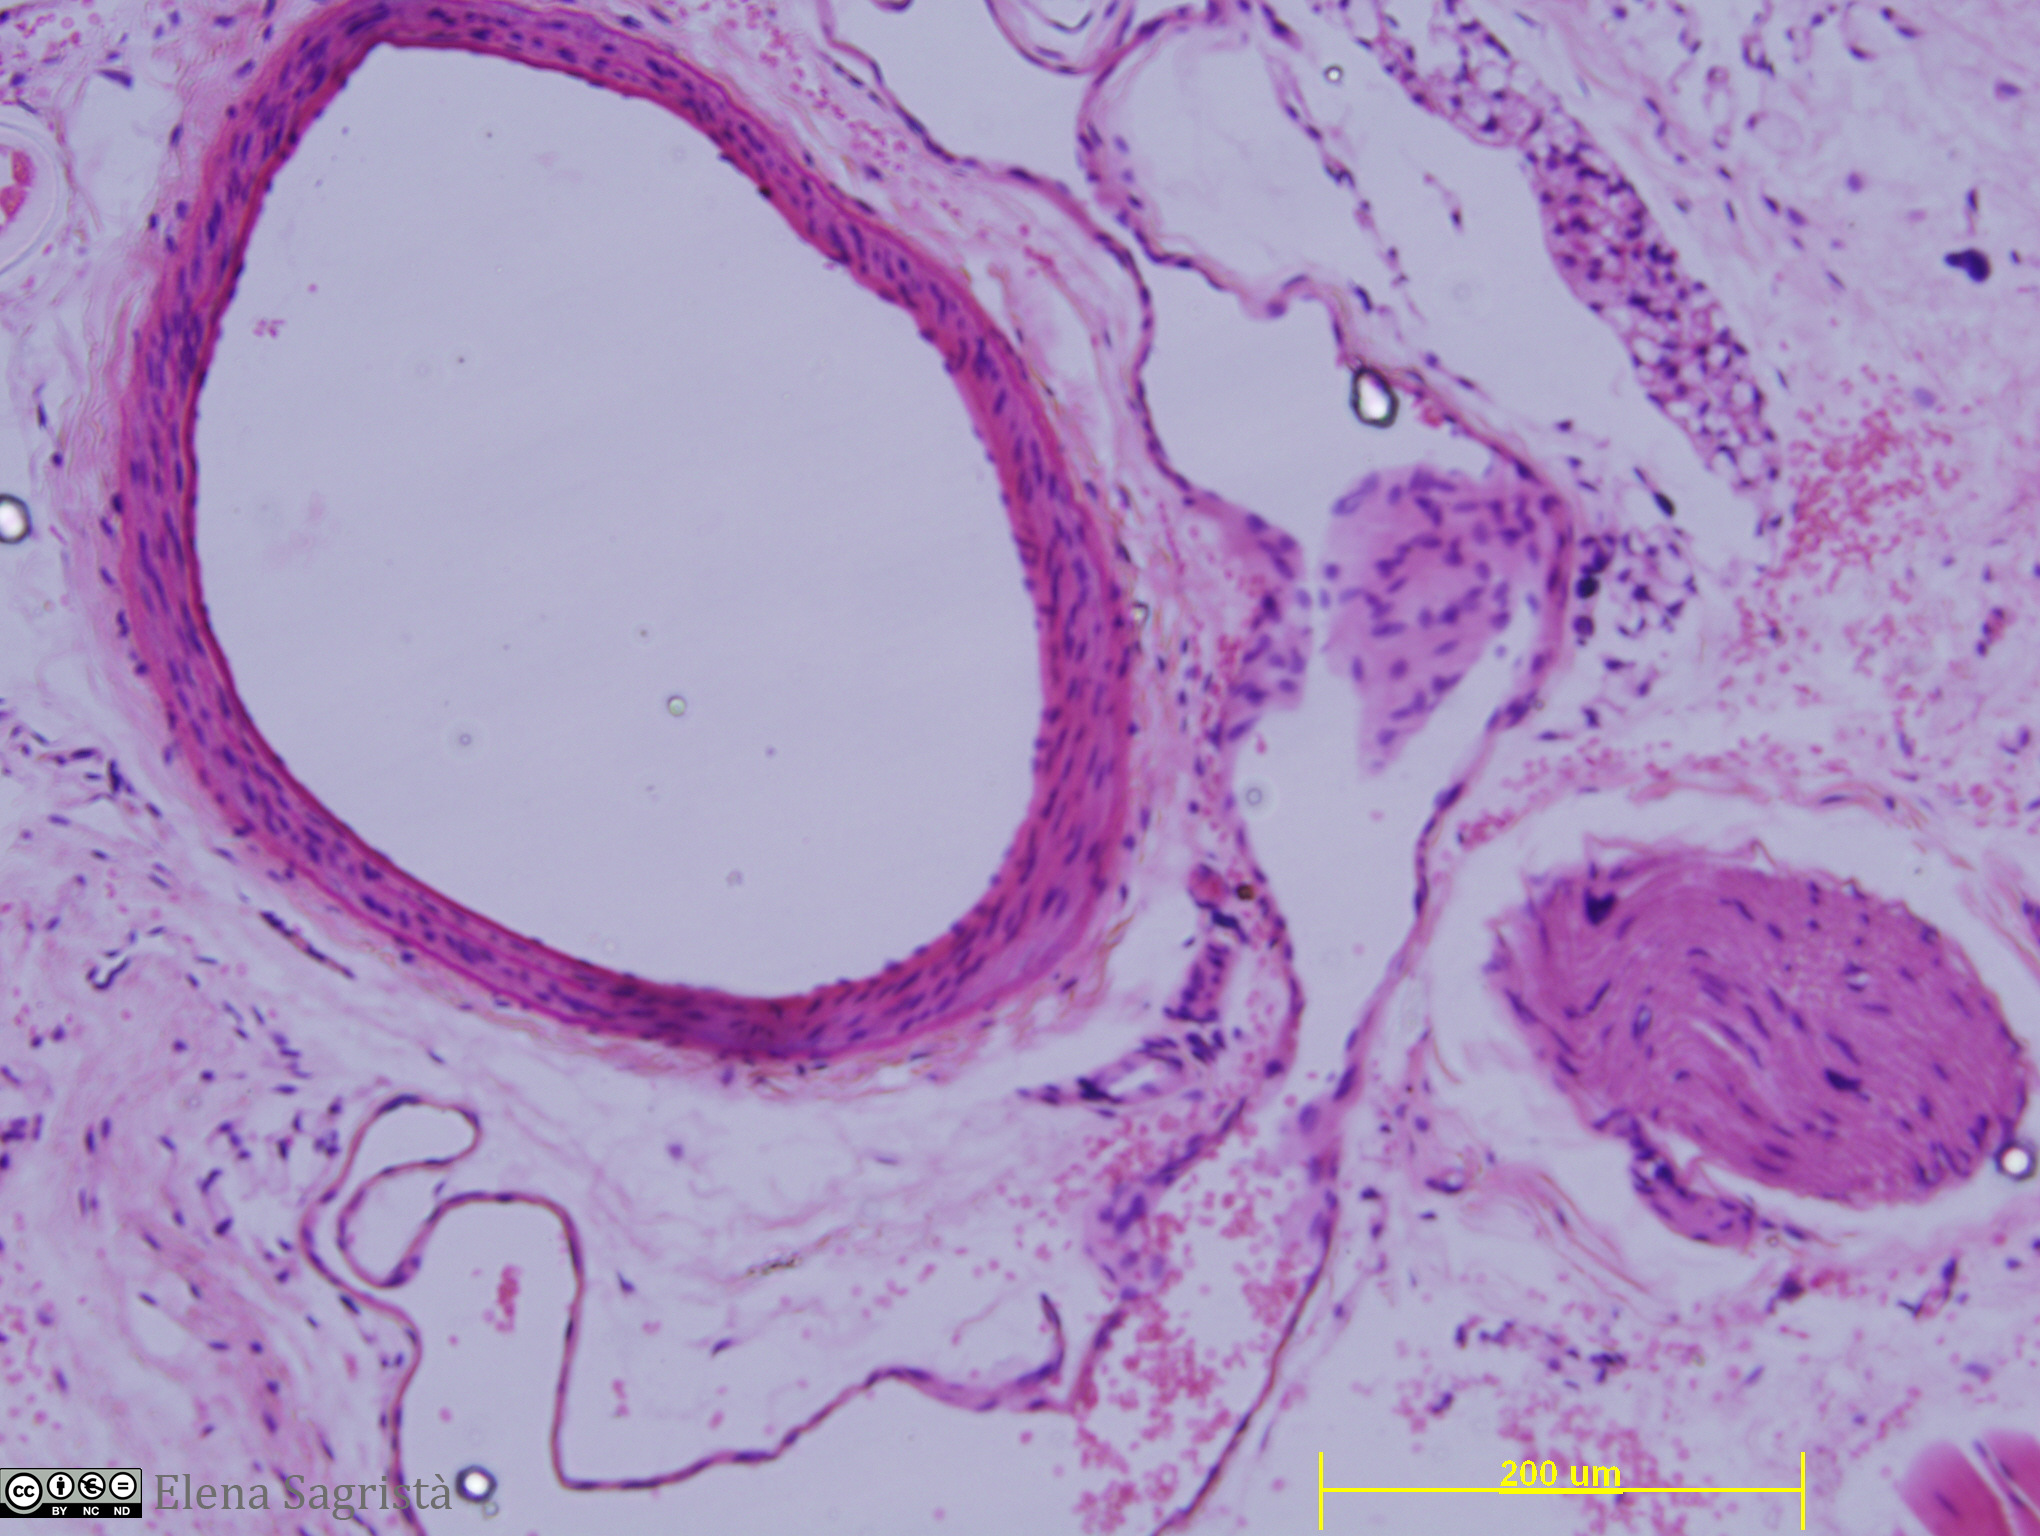

Imatges de preparacions histològiques de teixit epitelial. Microscopia òptica.